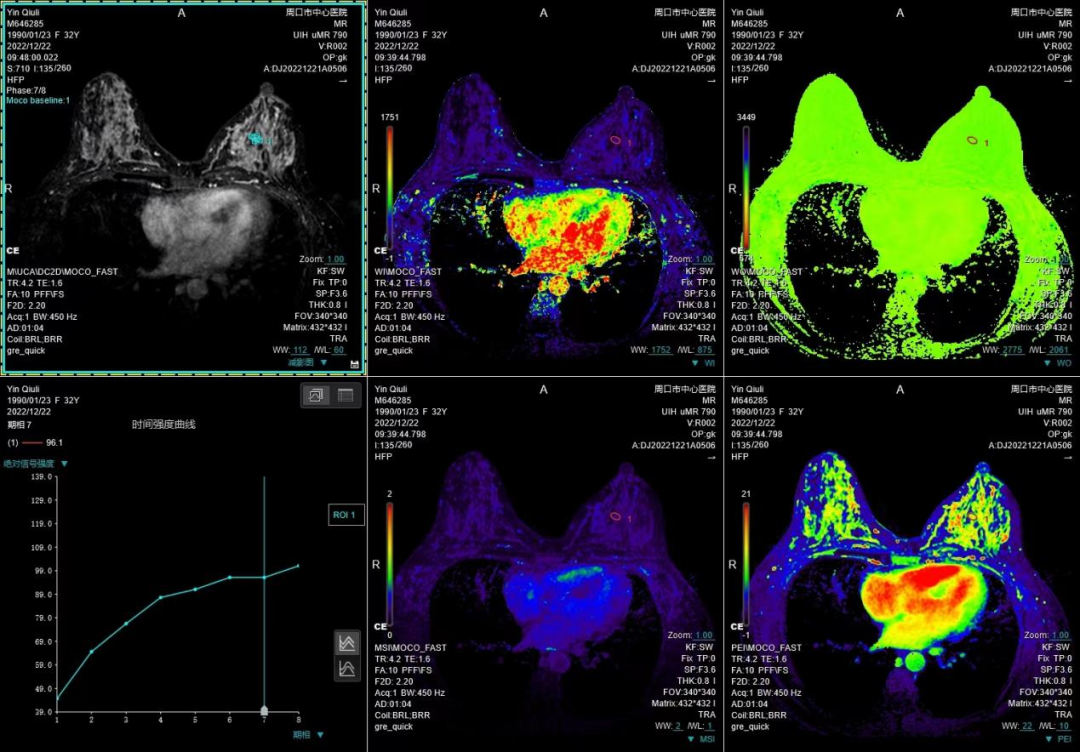

联影磁共振怎么样开启高精度诊断新模式!联影光梭3.0T磁共振落户周口市中心医院_https://www.jmylbn.com_新闻资讯_第6张

(乳腺多模态成像)